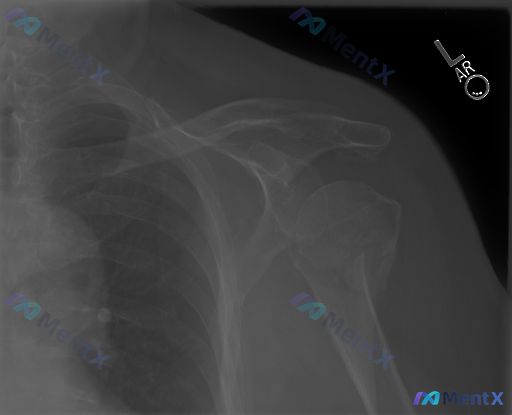

左肩部正位X光片:这个病例的第一判断与下一步怎么走?

整理了一份左肩部正位X光片的影像分析资料,先不说最终结论,大家看看这份资料里的核心异常、第一判断会往哪边靠?

- 最显眼的骨骼异常是什么?

- 有没有可能是病理性骨折?

- 下一步最想补什么检查?